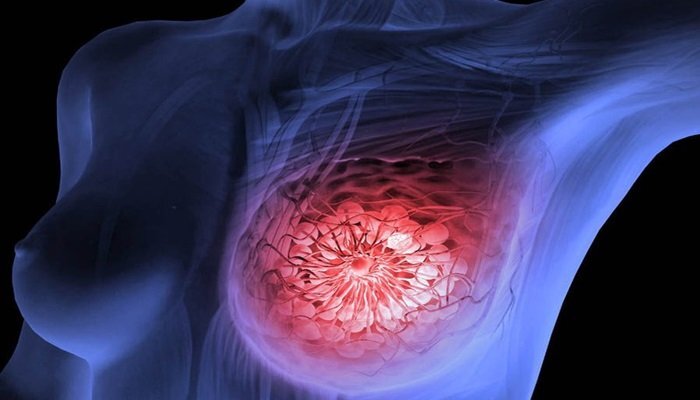

Sau khi thấy đau nhói và sờ thấy hạch ở ngực, V. tới bệnh viện khám và phát hiện ra sự thật, V. bị ung thư vú - căn bệnh ung thư phổ biến nhất ở nữ giới hiện nay.

Sau khi thấy đau nhói và sờ thấy hạch ở ngực, V. tới bệnh viện khám và phát hiện ra sự thật, V. bị ung thư vú - căn bệnh ung thư phổ biến nhất ở nữ giới hiện nay.

Độ tuổi mắc ung thư vú trên thế giới thường là trên 60 tuổi, tuy nhiên ở Việt Nam là độ tuổi 40, thậm chí, các bác sỹ từng gặp trường hợp chỉ 20, 21 tuổi đã bị ung thư vú.